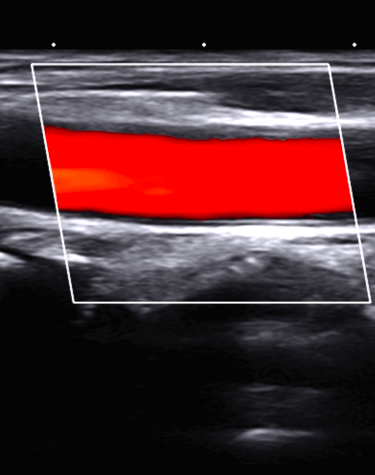

Por el costo de una ecografia, aprovechando nuestros conocimientos, experiencia y tecnologia te exploramos el abdomen total, el tiroides y carotidas

ECOGRAFIA O ULTRASONIDO DE TODO EL CUERPO

Ultrasonido y Densitometría

Estudios de ultrasonido y densitometría para un diagnóstico completo y detallado.

Ultrasonido o Ecografia

APLICA PARA : CABEZA, CUELLO, TORAX, ABDOMEN Y EXTREMIDADES

PARA TODAS LAS ESPECIALIDADES

PIONEROS CON MAS DE 40 AÑOS DE EXPERIENCIA

REALIZADA POR EXPERTOS

Galería Médica

Explora nuestros servicios de radiología y medicina regenerativa.